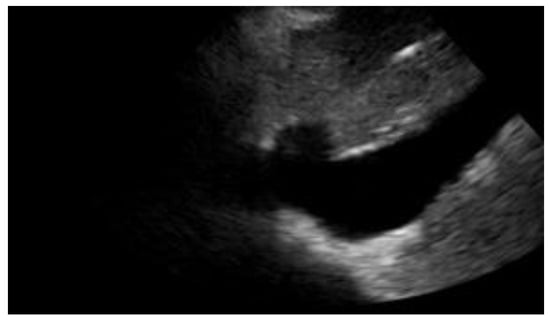

While we will discuss heart failure further in the chapter on thoracic POCUS, it is worth noting that the evaluation of the IVC (Figure 2) can help us in several respects, as its diameter and collapsibility reflect the systemic volume state (Table 1) [16,17].

Figure 2. Subcostal longitudinal view: normal IVC.

A reduction in diameter accompanied by an increase in collapsibility orients us, for instance, towards a state of hypovolemia, while an increase in caliber and a smaller excursion during inspiration indicates congestion. For this reason, finding a congested IVC may suggest fluid overload and lead to a diagnosis of heart failure [18] (Figure 3).